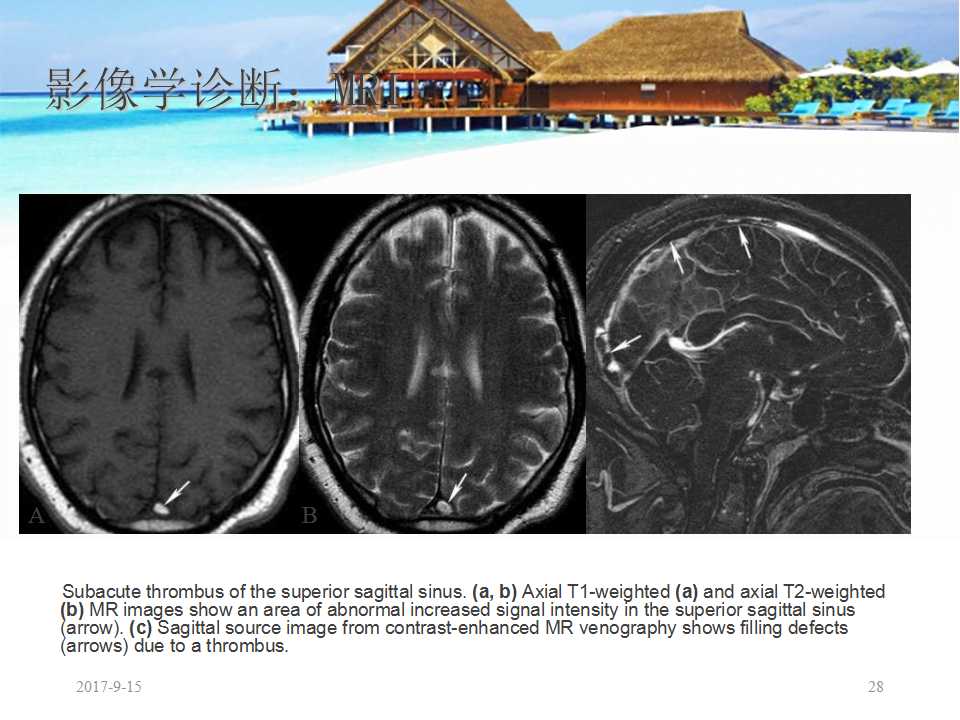

二、头颅 MRI/MR静脉成像(MRV)

可直接显示颅内静脉和静脉窦血栓,以及继发于血栓形成的各种脑实质损害,较 CT 更为敏感和准确,但血栓表现随发病时间不同而变化,其中又以亚急性期的血栓高信号对 CVST 诊断较为可靠。磁敏感加权成像( SWI )或 T2* 加权梯度回波( T2*GE ) 等序列较 MR 常规序列对显示脑内出血更加敏感,对诊断 CVST 比常规系列成像具有更高的敏感度和特异度。头颅 MRV 可发现相应的静脉窦主干闭塞,皮质静脉显影不良,侧裂静脉等侧支静脉扩张,板障静脉和头皮静脉显像等征象。在大多数情况下, MRI/MRV 已可对 CVST 进行准确诊断,且所用增强剂更安全又没有 X 线辐射,被认为是诊断和随访 CVST 的最佳手段,但局部单纯的皮质静脉显示能力较弱,以及不能判断静脉血流方向是其主要不足之处。在 MRV 发现一侧静脉(窦)血流缺失时,并不能判断是由于血栓或是先天闭塞所造成。有研究者建议,若 CT 上双侧下颌切迹对称则支持 CVST 的诊断。 MRV 包括时间飞跃 MRV ( TOF MRV )、相位对比血管成像( PCA )和对比增强 MRV ( CE MRV ) 3 种成像方法,与 TOF MRV 和 PCA 相比, CE MRV 由于消除了血管内湍流,使颅内静脉和静脉窦显示更为清晰,如同时结合数字减影 MRA ( DSMRA )和最大密度投影( MIP )重建等技术,可多角度显示静脉血管的三维影像,因此, CE MRV 可作为 MRV 的首选成像方法。